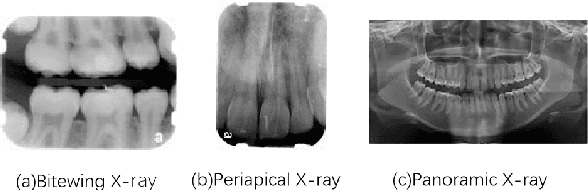

Abstract:Analysis of dental radiographs is an important part of the diagnostic process in daily clinical practice. Interpretation by an expert includes teeth detection and numbering. In this project, a novel solution based on adaptive histogram equalization and convolution neural network (CNN) is proposed, which automatically performs the task for dental x-rays. In order to improve the detection accuracy, we propose three pre-processing techniques to supplement the baseline CNN based on some prior domain knowledge. Firstly, image sharpening and median filtering are used to remove impulse noise, and the edge is enhanced to some extent. Next, adaptive histogram equalization is used to overcome the problem of excessive amplification noise of HE. Finally, a multi-CNN hybrid model is proposed to classify six different locations of dental slices. The results showed that the accuracy and specificity of the test set exceeded 90\%, and the AUC reached 0.97. In addition, four dentists were invited to manually annotate the test data set (independently) and then compare it with the labels obtained by our proposed algorithm. The results show that our method can effectively identify the X-ray location of teeth.